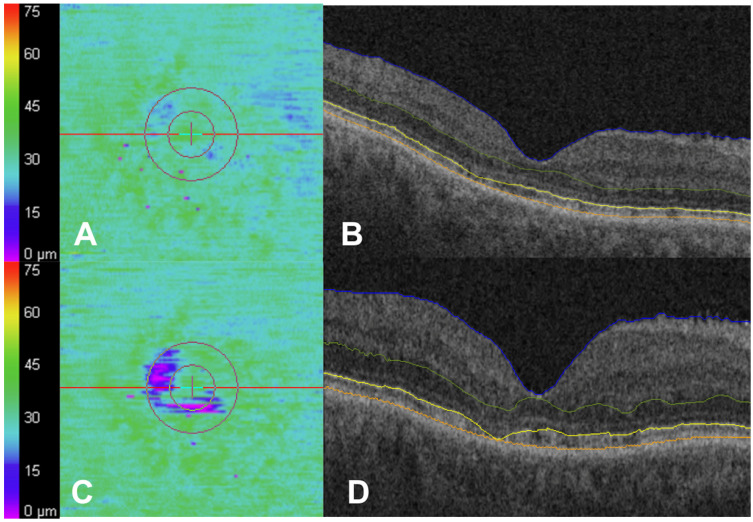

背景/目的:羟基氯喹(HCQ)视网膜病变可能在早期被忽视,因为OCT的结构改变可能先于症状出现,而且往往很微妙。早期发现对于防止不可逆转的损害至关重要。本研究利用椭球区(EZ)作图评估HCQ明显中毒前的纵向OCT变化。方法:长期HCQ患者至少间隔一年使用Cirrus HD-OCT进行两次黄斑立方体扫描。扫描结果用EZ-mapping平台进行分析,并进行人工验证。有基线OCT毒性体征或同时存在黄斑疾病的患者根据隐蔽性专家评价被排除。结果:纳入373例患者373只眼。平均年龄57.0±12.6岁,平均HCQ剂量379.4±59.4 mg,治疗时间5.6±3.7年,OCT间隔3.1±0.9年。视网膜外指标在整个队列中保持稳定。平均表面EZ衰减从3.3%增加到3.9% (p = 0.24)。34只眼(9.1%)EZ衰减绝对增加≥4% (~1.5 mm2)。这种增加与HCQ开始时的年龄(p < 0.001)、第一次和第二次OCT时的年龄(p < 0.001)、基线视力(p = 0.01)以及其他视网膜外指标的变化(p < 0.01)显著相关。在第二次10月时,只有3/34只眼(8.9%)被管理临床医生诊断为HCQ毒性。然而,经专家评审,其中26只眼(76.5%)有HCQ毒性体征,这表明与临床医生评审相比,这些定量视网膜外指标检测毒性的总体灵敏度更高。结论:纵向OCT评估显示,HCQ眼的视网膜外指标总体稳定,但有一部分EZ衰减增加,这与HCQ开始时的年龄、基线视力和专家OCT检查相关。这些变化可能有助于识别有风险的眼睛和早期毒性的眼睛,并值得进一步验证作为潜在的筛选生物标志物。

Background/Objectives: Hydroxychloroquine (HCQ) retinopathy can be underrecognized early, as structural changes in OCT may precede symptoms and are often subtle. Early detection is crucial to prevent irreversible damage. This study evaluated longitudinal OCT changes preceding overt HCQ toxicity using ellipsoid zone (EZ) mapping. Methods: Patients on long-term HCQ underwent two macular cube scans at least one year apart using Cirrus HD-OCT. Scans were analyzed with an EZ-mapping platform and manually validated. Patients with baseline OCT signs of toxicity or co-existing macular disease were excluded based on masked expert review. Results: Three hundred and seventy-three eyes of 373 patients were included. The mean age was 57.0 ± 12.6 years, the mean HCQ dose was 379.4 ± 59.4 mg, the treatment duration was 5.6 ± 3.7 years, and the OCT interval was 3.1 ± 0.9 years. Outer retinal metrics remained stable across the cohort. The mean en face EZ attenuation increased from 3.3% to 3.9% (p = 0.24). Thirty-four eyes (9.1%) experienced an absolute increase of ≥4% (~1.5 mm2) in EZ attenuation. This increase was significantly associated with age at HCQ initiation (p < 0.001), age at the time of the first and second OCT (p < 0.001), and baseline visual acuity (p = 0.01), and demonstrated changes in other outer retinal metrics (p < 0.01). Only 3/34 eyes (8.9%) were diagnosed by the managing clinician with HCQ toxicity at the time of the second OCT. However, 26 of these eyes (76.5%) had signs of HCQ toxicity by expert review, suggesting the overall greater sensitivity of these quantitative outer retinal metrics for detecting toxicity compared with clinician review. Conclusions: Longitudinal OCT assessment revealed overall stability in outer retinal metrics in eyes on HCQ, but a subset showed increased EZ attenuation, which correlated with age at the time of HCQ initiation, baseline visual acuity, and expert OCT review. These changes may help identify at-risk eyes and eyes with early toxicity and warrant further validation as potential screening biomarkers.